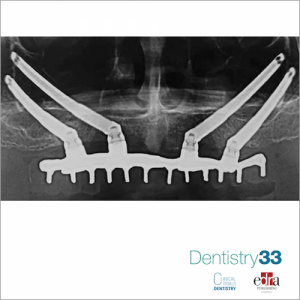

When bone volume is insufficient for implant placement, bone regeneration techniques can be used or the insertion of particularly inclined implants or zygomatic implants. The survival of implants placed in the posterior maxilla is dependent on the biomechanical characteristics of bone around the implant as high occlusal forces are developed in the molar region during mastication. These forces can also induce prosthetic complications, including fracture of the prosthesis, fracture of the screw and bone loss, especially when cantilevered prostheses are provided. The pterygomaxillary area has tended to never be much considered as a region suitable for implant placement. This region is often associated with both extensive bone degeneration (poor bone quality) and a reduced amount of cortical bone. In 1989, Tulasne8 described a method for inserting and engaging pterygoid implants in the cortical bone formed by the posterior wall of the maxillary tuberosity, horizontal process of the palatine bone, and pterygoid process of the sphenoid bone. Pterygoid implants are attractive because of the availability of dense cortical bone for engagement of the implant. They also help to

overcome the need for maxillary sinus lift or grafting procedures, reducing treatment time and allowing immediate loading of the implant. In addition, pterygoid implants allow the prosthesis to have sufficient posterior extensions, eliminating the need for distal cantilevers. Disadvantages of pterygoid implants include:

In an Italian study, published on Journal of Prosthetic Dentistry, July 2021, the authors investigated the 1-year survival and success rates of pterygoid implants and prostheses in patients with severe posterior maxillary atrophy who required immediate fixed prosthesis for full arch. Fifteen participants were enrolled in the study, completely edentulous or with limited dentition in the maxillary arch and with severe atrophy of the posterior maxilla. Implant survival data were assessed at abutment connection time by mobility testing for each implant. After the placement of the prosthesis, survival was assessed by maintaining the marginal bone through panoramic radiographs, and the absence of pain or symptoms of infection was recorded. The t-test was used to assess the age difference between men and women (a = .05). Correlations between categorical variables (Fisher's exact test) were used to evaluate the possible association between the number of implants and the patient's age and the presence of comorbidities (a = .05)

During the 1-year follow-up, high stability of the prosthesis and no loss of implants was observed for all participants. No patient reported any pain or paraesthesia. No peri-implant radiolucency was detected in the panoramic radiographs. The survival and success rates in the follow-up period were 100%.